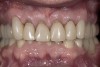

Figure 10  The final restorations demonstrate the esthetic and functional changes from lengthening the incisal edges and raising the gingiva.

Figure 10

There are several methods for identifying the correct incisal edge position pre-surgically, including the use of an overlay matrix, altering the contour of the existing teeth using reshaping or bonding, and preparing the teeth and placing temporaries.15 The patient who almost always requires tooth preparation and temporaries in order to correctly identify the incisal edge position is the one with severe wear and a need for the addition of significant length to the incisal edge of the existing teeth. Because there are such significant functional concerns in altering the incisal edge position of these patients, using a simple removable overlay to identify the esthetic position of the incisal edge and gingiva is risky. Instead, it is much more predictable to lengthen the teeth temporarily to evaluate the esthetic and functional success of the new incisal edge position prior to any crown lengthening. If the teeth are amenable to direct bonding to alter incisal edge position, this is often the best approach to temporization. If, on the other hand, the teeth are severely worn and bonding is not realistic, it will probably be necessary to prepare them and place temporaries to evaluate the change. Once it becomes clear that the new incisal edge position is acceptable both esthetically and functionally, the periodontal surgery can be completed to correct gingival levels and, therefore, crown length (Figure 6, Figure 7, Figure 8, Figure 9 and Figure 10).